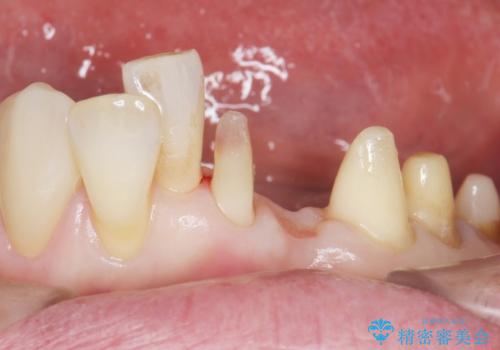

精査したところ、前歯の咬み合わせが反対になっていること、下の奥歯(下顎両側67)が4本欠損していることから動揺が生じていました。

入れ歯も抵抗があるとのことから、相談を重ね、今の状態では保存不可能な下の前歯(左下2)を抜去し、ブリッジや連結補綴により動揺を抑えることにしました。

下顎大臼歯が欠損したままで今ある歯に負担がかかりやすいことから、長期的予後は保証できないことをご理解頂いた上で治療を行いました。